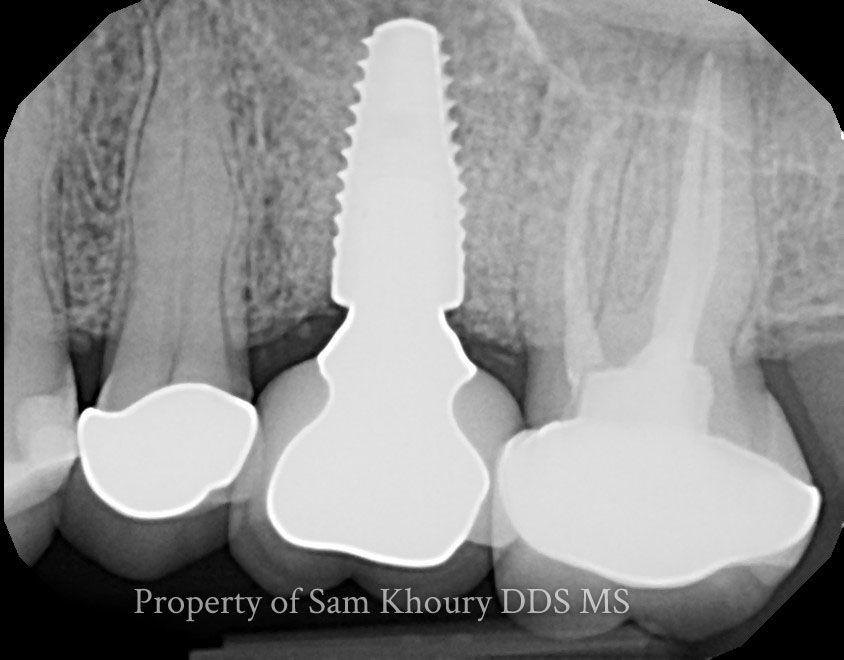

Multiple Dental Implants